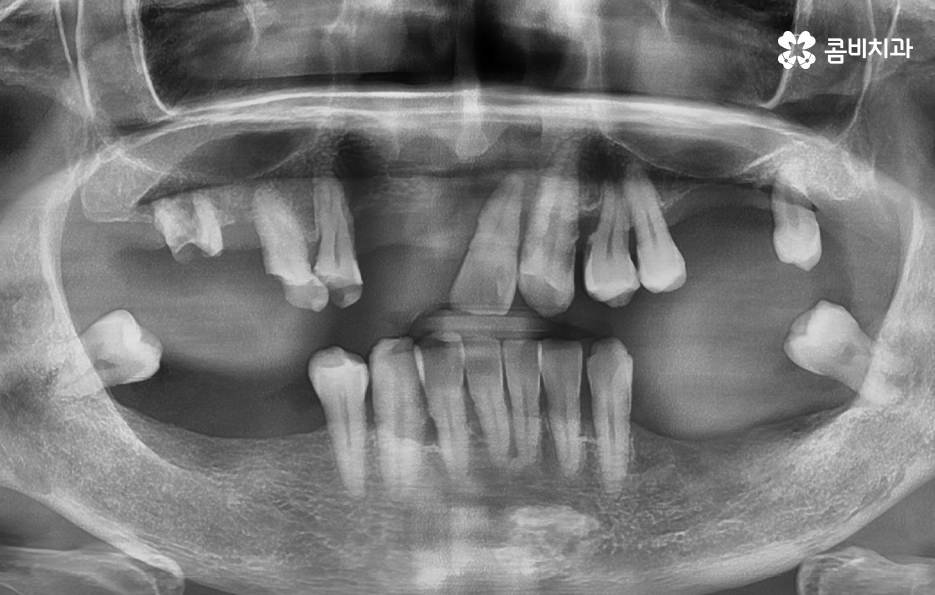

노년기에 치아 상실이 증가하는 큰 원인은 치주염의 장기적 누적 효과로서 치주염은 잇몸 염증이 잇몸뼈까지 파고들어 뼈를 녹여 치아를 지탱하지 못하게 만드는 병으로 젊을 때는 잇몸이 어느 정도 회복되기 때문에 크게 느껴지지 않지만, 나이가 들수록 회복 속도는 느려지고 염증은 더 빨리 확산되며 잇몸뼈가 한 번 녹기 시작하면 다시 원래 그대로 회복되는 것은 사실상 어렵기 때문에 치아는 점점 흔들리고, 결국 발치까지 이어질 수 있어요

노년기 환자분들의 상당수는 갑자기 치아가 흔들리기 시작했다고 이야기하지만 실제로는 오랜 기간 진행된 치주염이 임계점에 도달한 결과로서 치주염은 조용히 진행되기 때문에 정기 검진이 없으면 치아 상실까지 이어지는 경우가 많이 나타나고 있었어요

그리고 충치 재발 또는 오래된 보철물의 노후화 문제도 큰데 젊은 시절 충치 치료나 크라운, 브릿지 등을 했더라도 노년이 되면 재 치료가 필요한 경우가 많으며 보철물은 영구적이지 않기 때문에 접착력이 약해지거나 잇몸이 내려가면서 보철물 경계부위에 충치가 다시 생길 수 있고 특히 치아 뿌리 부분에 생기는 충치는 진행 속도가 빨라 치료가 어려운 경우도 많아서 보철물 아래 치아가 불안정해지면 결국 발치해야 하는 상황이 생기는 거예요.